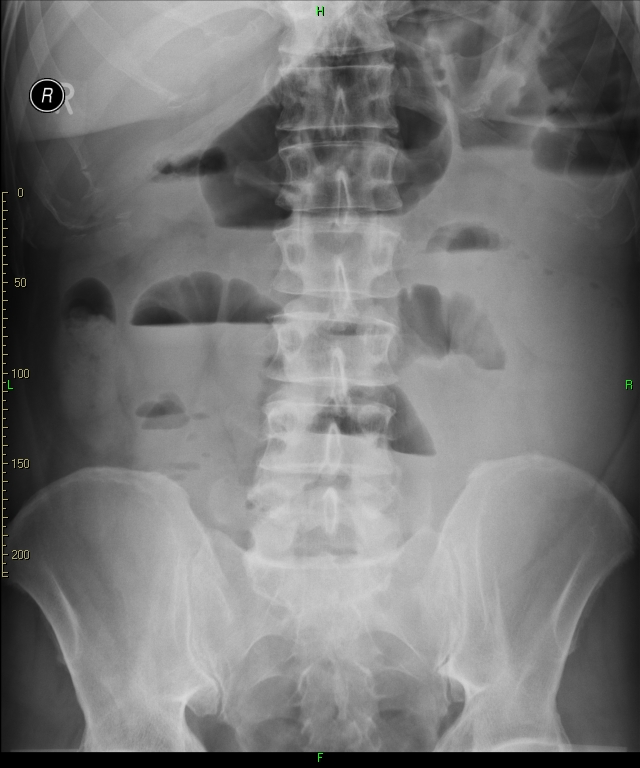

• Plain abdominal radiographs are usually sufficient to raise suspicion for bowel obstruction. In most cases, the radiologic appearance is indicative of the level of the blockage (stomach, small or large bowel). Mechanical obstruction can be incomplete but also it can become complete as the passage function wears off in the strain. Clinical data and patient history (previous abdominal surgery, medication, cancerous state etc.) are all important details in order to help to differentiate the types of obstruction from one another.

21. Right image: plain abdominal X-ray showing distended bowel loops, with wide air-fluid levels. Left image: plain abdominal radiograph showing distended colon until the sigmoid segment, with wide air-fluid levels. The obstruction is most likely to be at the level of the sigmoid or the rectum.